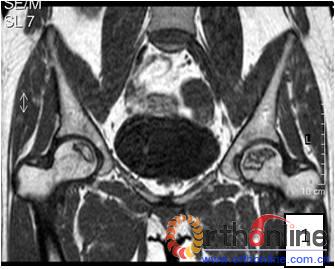

2.2 影像学结果 影像学结果与临床结果基本同步。临床结果优的36髋,34髋维持圆形且修复较完全(图1)。1例双髋Ⅲa激素性(SARS患者)ONFH,术后随访7年8月,X线片显示股骨头虽不圆,但临床HHS评分90分为优(图2)。功能为良的12髋,7髋股骨头不圆,但股骨头与髋臼匹配好,其余5髋股骨头维持圆形。临床评定为差的17髋,股骨头均有超过4mm塌陷,股骨头与髋臼匹配不好,股骨头内无折断,MRI未显示骨髓水肿,关节间隙呈不对称改变,CT扫描示软骨下骨折,MRI显示骨髓水肿。

图2 男,22岁,激素性骨坏死,(1)双侧股骨头骨髓水肿,ARCO分期Ⅲa期,C3型;(2)X线片示股骨头塌陷,术前关节功能差(Harris评分50分);(3)打压植骨术(未加BMP2)后7年,关节功能好(Harris评分90分),股骨头有轻度塌陷,但头臼匹配好;(4)蛙式位显示股骨头臼匹配好